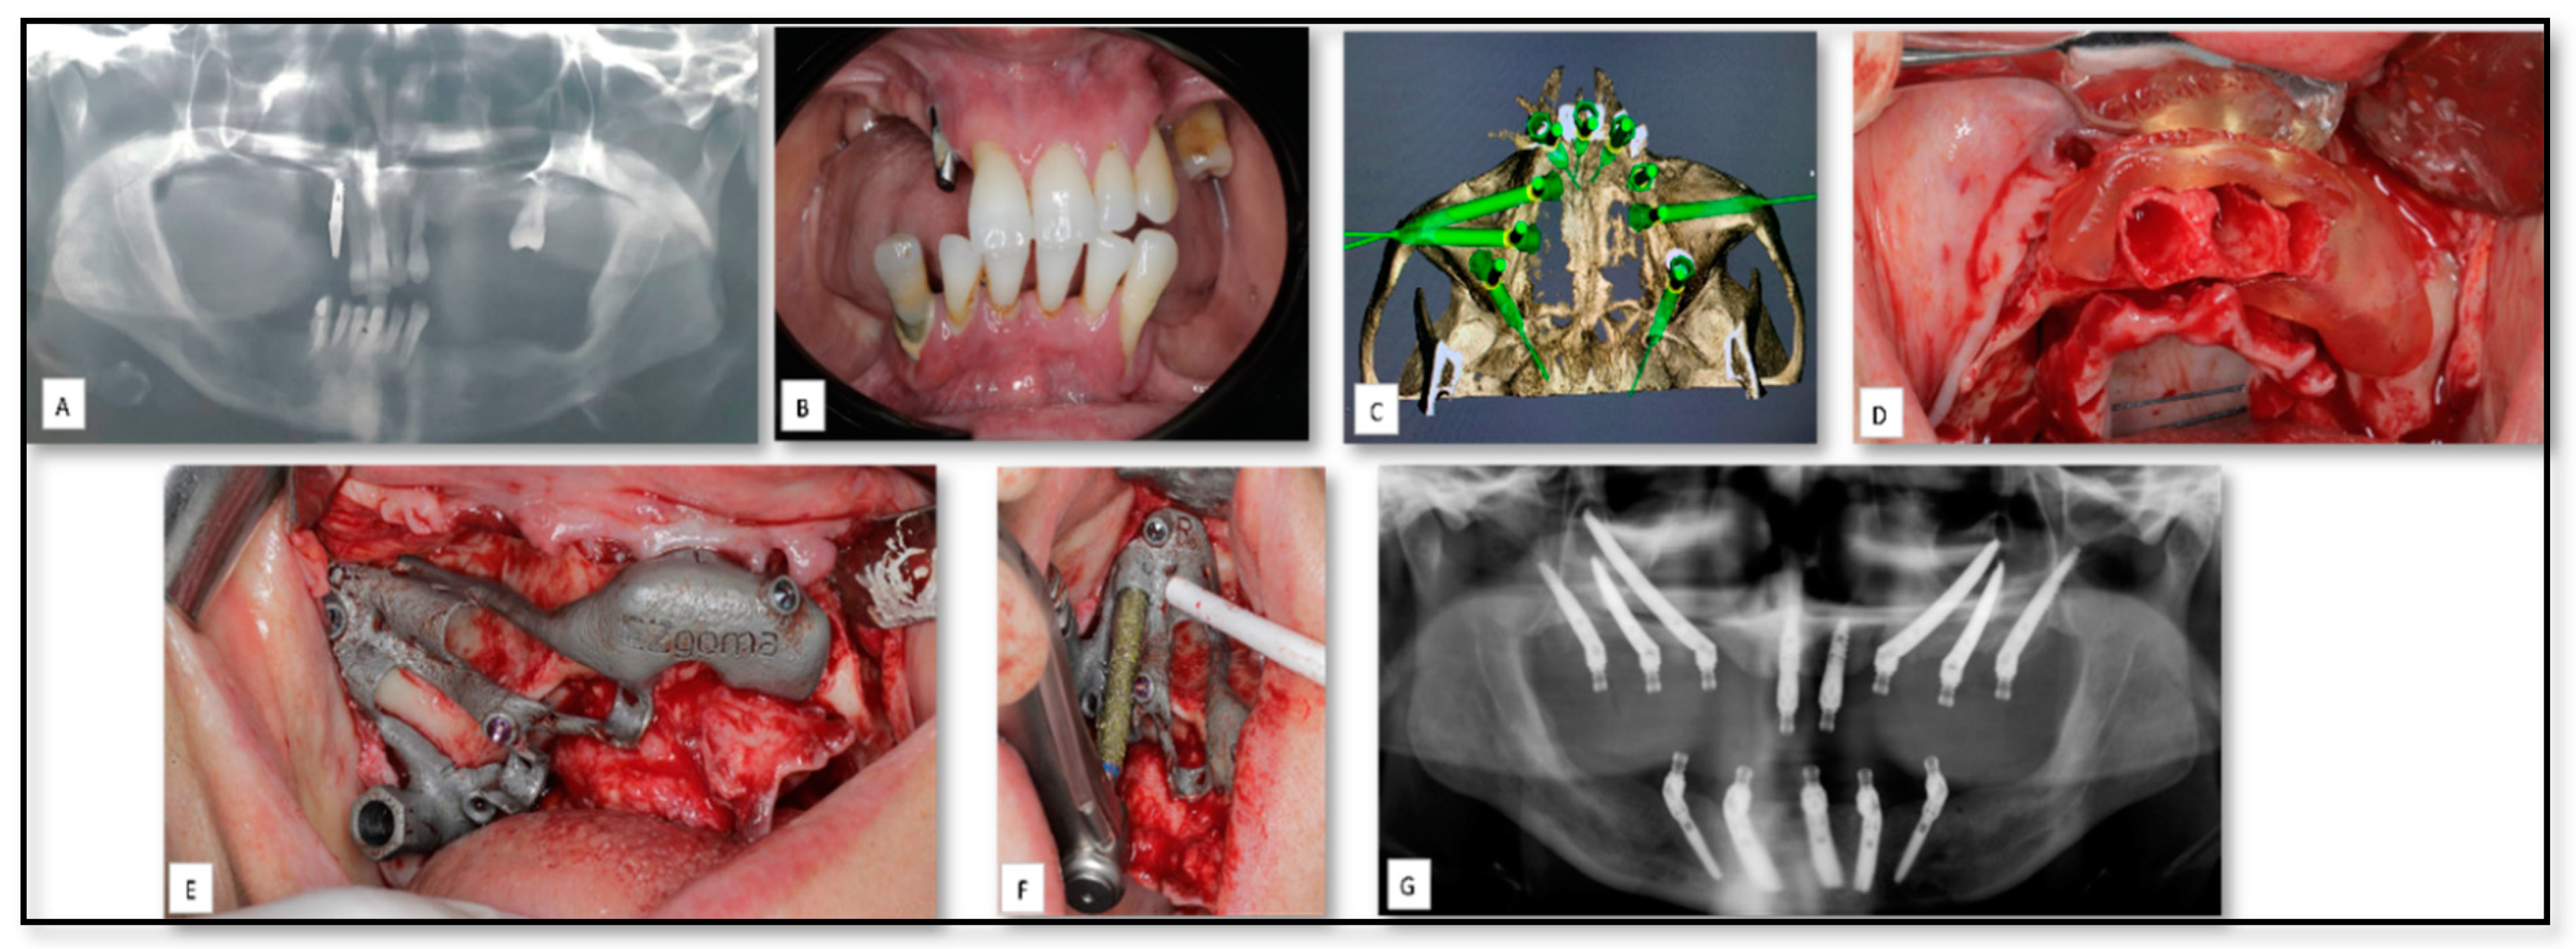

5.1. AM for Manufacturing of Surgical Guides for Zygomatic Implants Insertion

| 13 | 50 | F | Pre-prosthetics | Maxilla | Surgical guide stent | Titanium | − | |

| 14 | 71 | M | Pre-prosthetics | Maxilla | Surgical guide stent | Titanium | − | |

| 15 | 66 | F | Pre-prosthetics | Maxilla | Surgical guide stent | Titanium | − | |

| 16 | 56 | F | Pre-prosthetics | Maxilla | Surgical guide stent | Titanium | − |